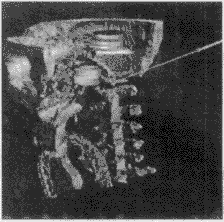

对手术方案的结果进行三维显示和多剖面显示是可视化的关键。系统考虑到各种显示方法的优缺点,对它们进行合理的运用和改进。对医生勾画的重要功能区采用面向多边形的表面显示算法,重建出的区域立体感强,图7是对医生勾画的眼球、视神经和脑干的重建结果。对于颅骨的显示,系统采用了直接投影的体显示法和改进的Marching Cube算法两种,后一种算法可弥补前一种算法对光照效果的过分依赖,而前一种算法则可弥补后一种算法过长的前处理时间的不足,供医生依情况选择,图8、图9为两种算法的显示结果。对于外皮肤的显示,系统综合利用面向多边形的显示方法和面向体素的表面显示方法,首先将构成外皮肤的所有像素自动提取出来,然后利用面向多边形的表面显示方法形成外皮肤,显示的图像比采用Marching Cube算法显示的更细腻、平滑,图10为显示结果。图11为一个复合显示结果。

图 7 勾画区域的三维重建(上下为不同角度)

图 8 直接投影的颅骨显示

图 9 改进MC的颅骨显示

图 10 综合两种表面显示重建的外皮肤

图 11 一个复合显示的结果